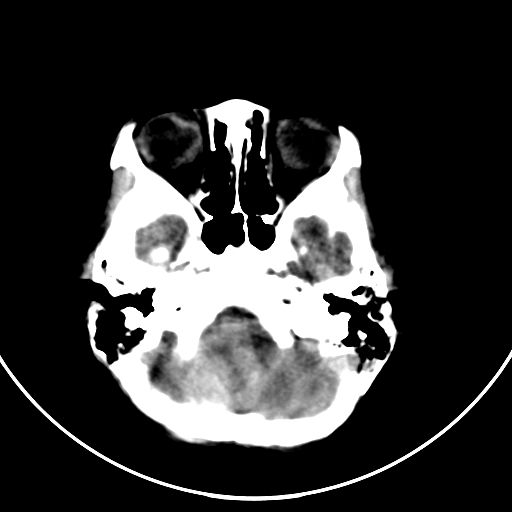

以下是引用zjzjr在2008-7-27 9:56:00的发言:[br]考虑髓母细胞瘤伴梗阻性脑积水.建议增强或mri

以下是引用子十在2008-7-27 9:53:00的发言:[br]考虑髓母细胞瘤